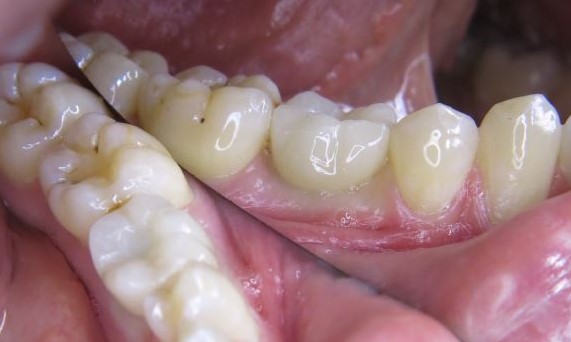

Exzellente Ästhetik

Langfristiger marginaler Knochenerhalt für eine exzellente Ästhetik über Jahre hinweg. Sie wissen, dass Sie gewonnen haben, wenn Ihr anspruchsvollster Patient dauerhaft zufrieden ist.

Langfristiger Knochenerhalt und exzellente Ästhetik dokumentiert und klinisch erprobt.